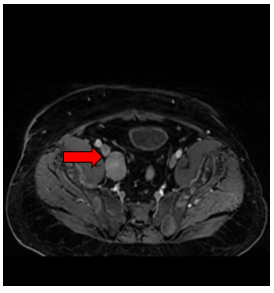

+ Các ổ tổn thương xương cùng, xương chậu, cổ xương đùi 2 bên, hạch cạnh bó mạch chậu bên phải kích thước 31x22mm - Theo dõi thứ phát

Hình 2. Hình ảnh chụp cộng hưởng từ tiểu khung: Hạch cạnh bó mạch chậu bên phải kích thước 31x22mm (mũi tên màu đỏ)